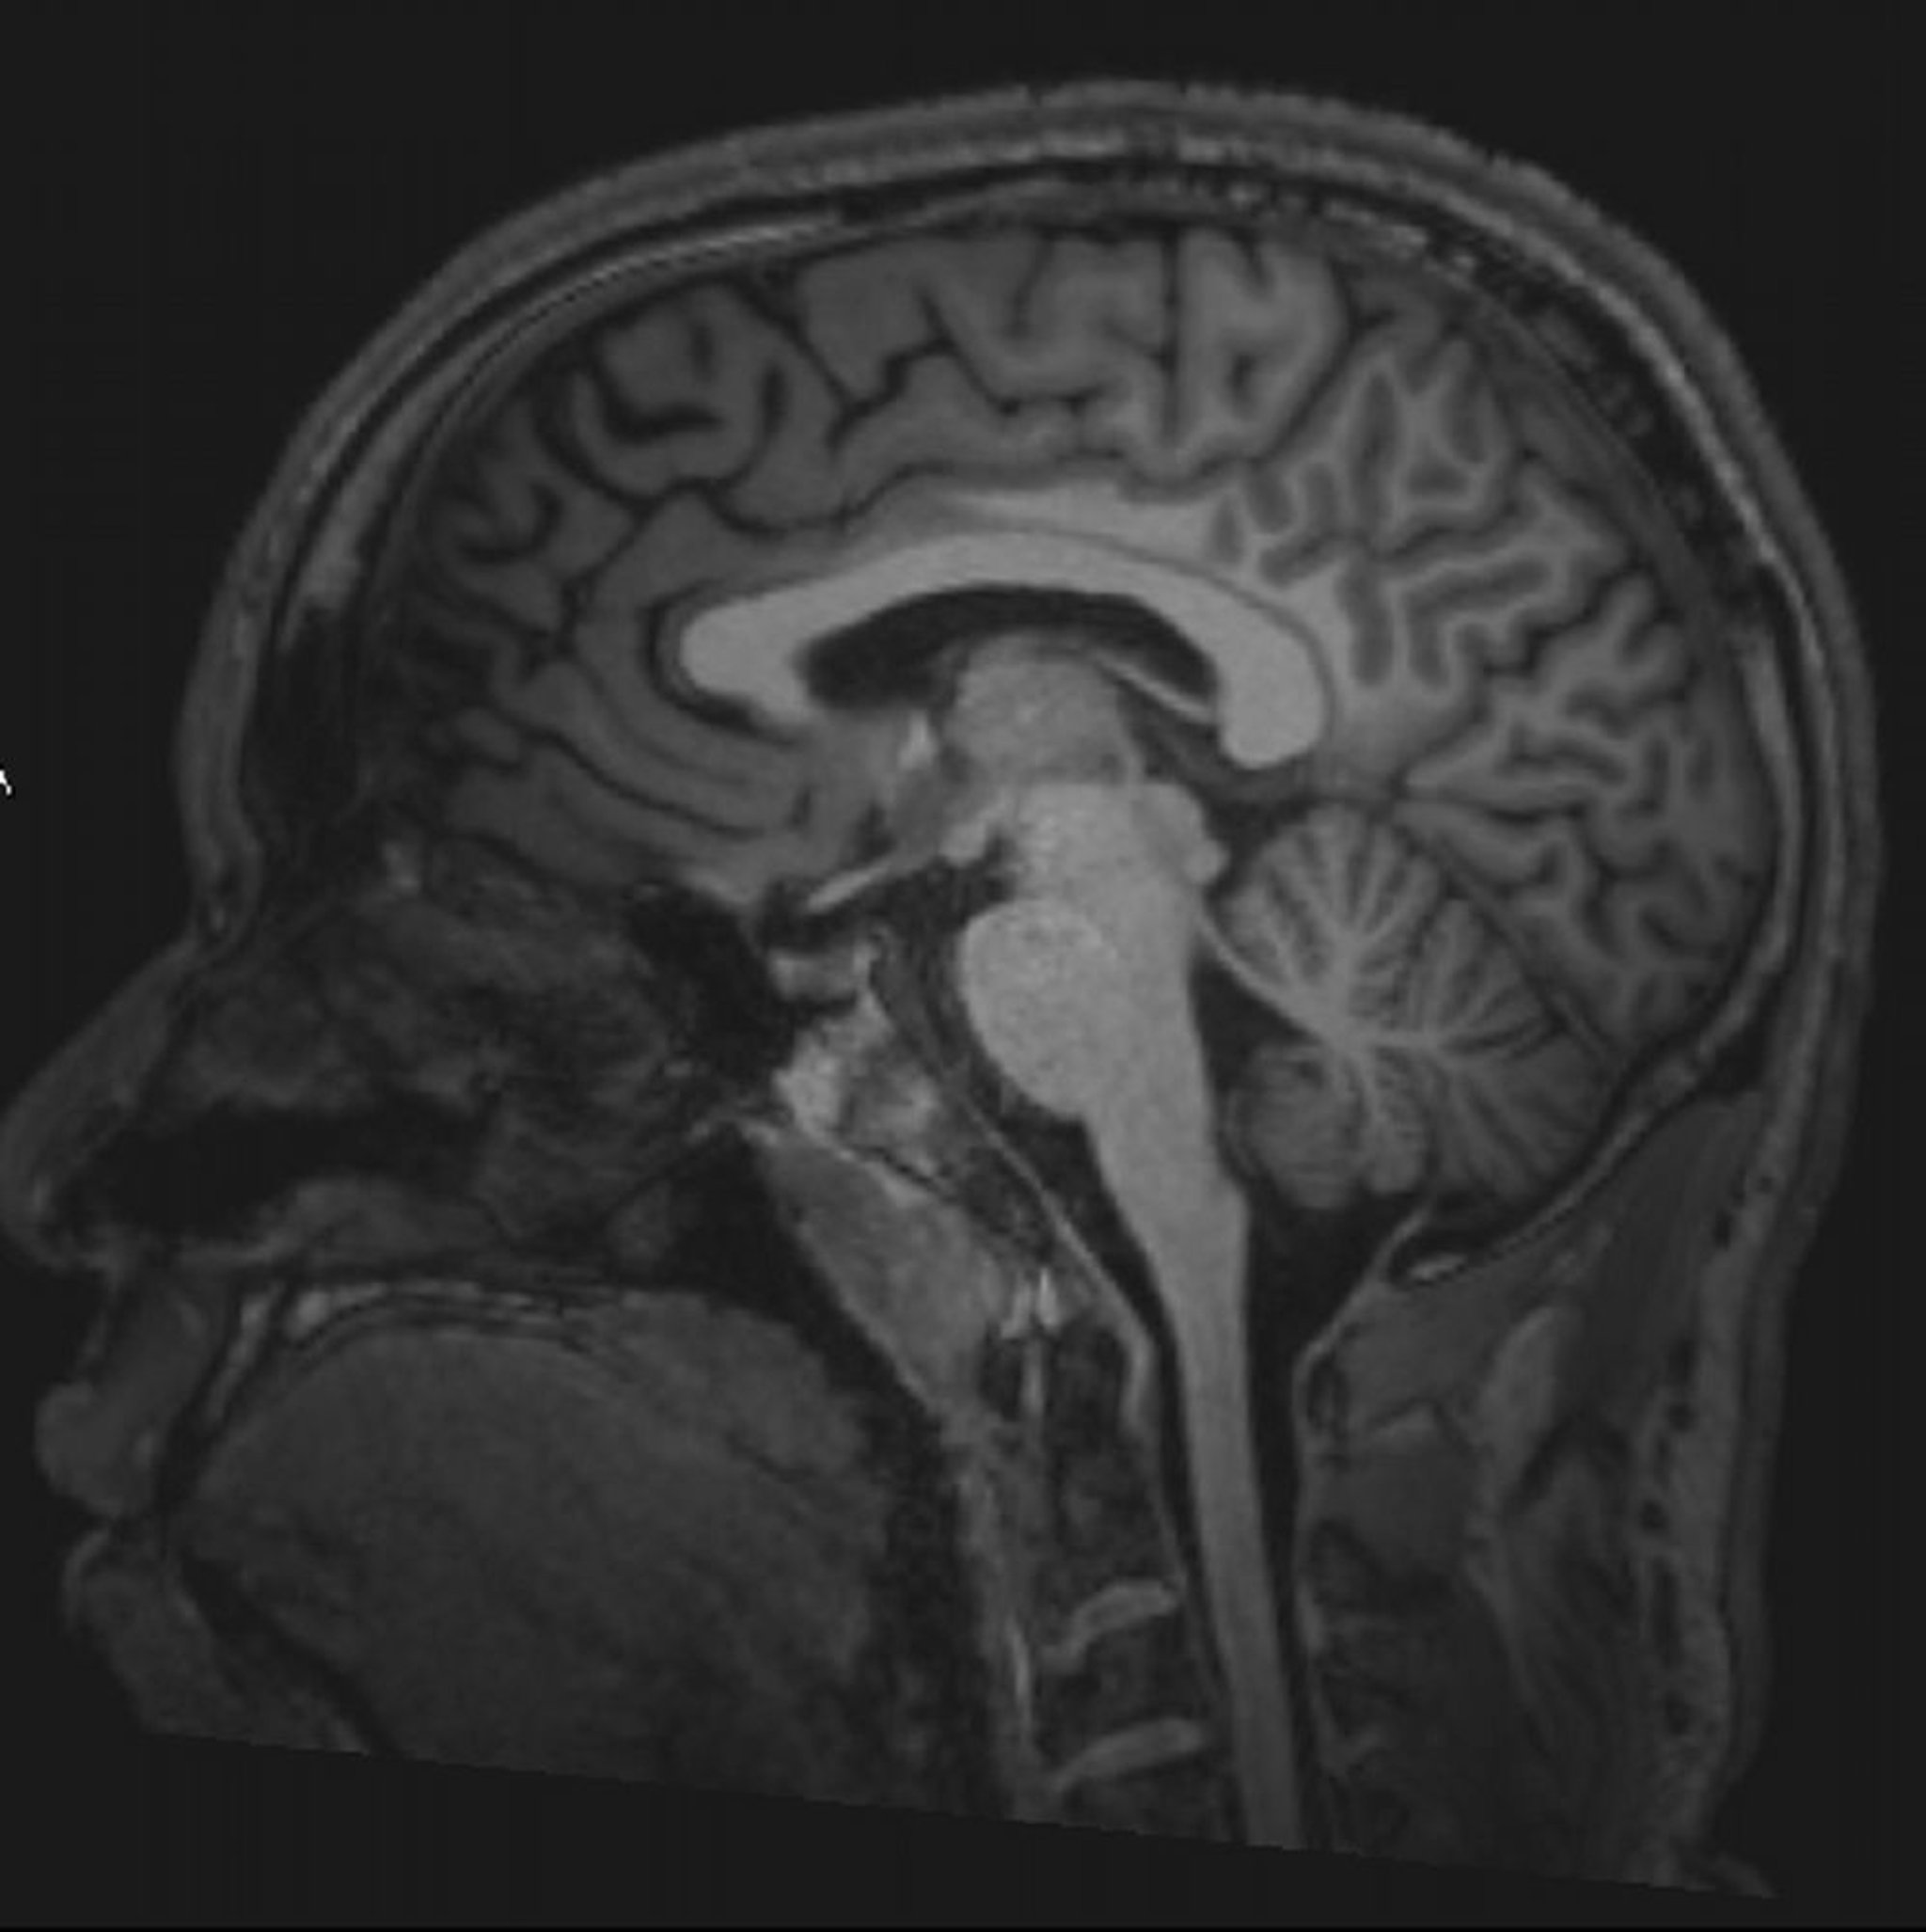

正常な脳MRI画像(矢状断像)―スライド3

© 2017 Elliot K.Fishman, MD.

神経疾患におけるMRI